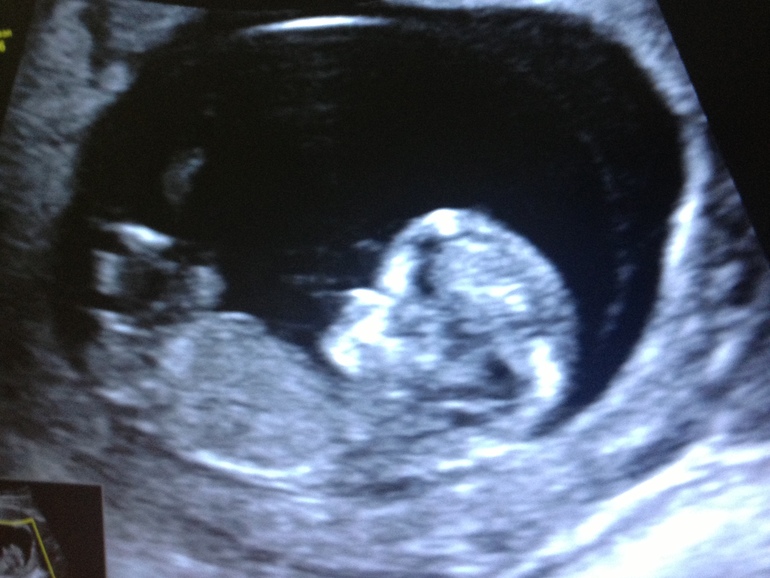

Я очень удивилась, когда в конце врач повернула ко мне монитор и дала посмотреть на моего маленького гуманоида. Правда, это была уже статичная картинка. А так хотелось увидеть всё в движении! Никаких снимков, конечно же, не дали. Правда, я сфотографировала монитор. Ну хоть что-то! Про пол тоже можно было даже не спрашивать. Врача сразу сказала, что еще рано для этого. В конце процедуры врач коротко сказала, что с ребенком всё хорошо, все показатели соответствуют сроку.

Весь вечер сидела и смотрела на фотографию)) Всё равно не верится, что это всё происходит со мной. Поскорее бы второй скрининг!